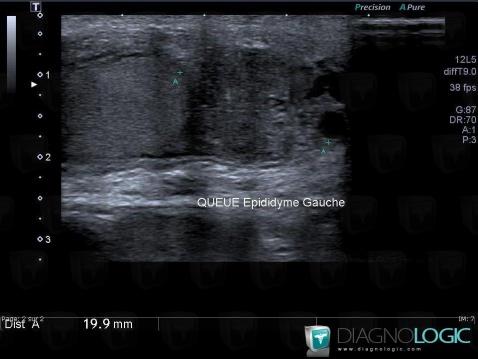

Voici les informations spécifiques à l'image clé ci dessus:

- Diagnostic épididymite, Localisation(s) Scrotum, comportant les gammes Lésion épididymaire, Masse solide extra-testiculaire